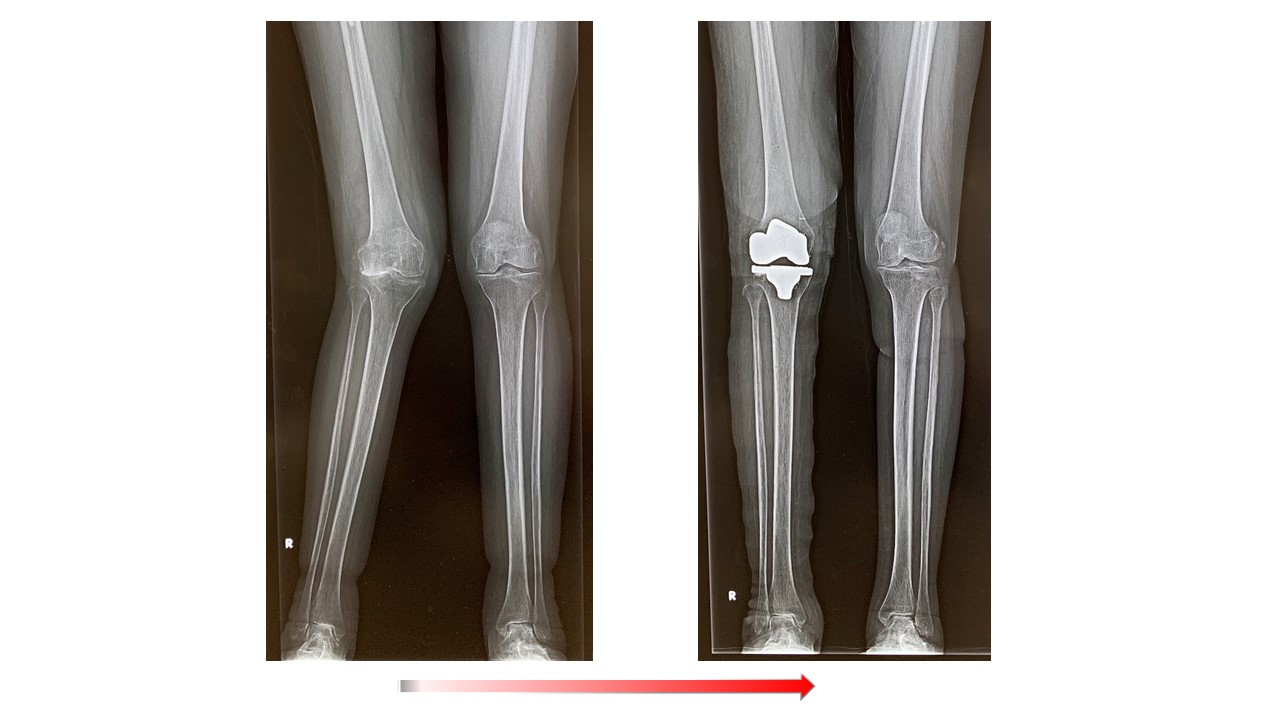

人工膝関節全置換術(単顆置換術)

人工膝関節全置換術(Total knee arthroplasty、TKA)ではナビゲーションシステムを使用して手術を行っています。より良い術後の満足度を得るため、生理的な膝のバランス、アライメントなどを考慮に入れた上で、術中の膝の状態をみながら、最適なインプラントの設置位置を決めて手術を行っています。そのため以前に比べてより使い易く違和感の少ない人工膝の再現が可能になっています。これらの術前検査として、立位での下肢全長のレントゲン検査やMRI検査、骨密度検査等も行いながら、最適なインプラントの選択を行います。さらに長期的には良好な骨の状態を保つことが重要ですので、術後も骨粗鬆症薬等につき外来でフォローアップ致します。紹介受診の場合はかかりつけのクリニックで骨粗鬆症薬の投薬を継続頂いてます。

また画像にあるようなシビアな症例でもしっかりと解剖学的・生理的に好ましい人工関節を設置することが可能です。